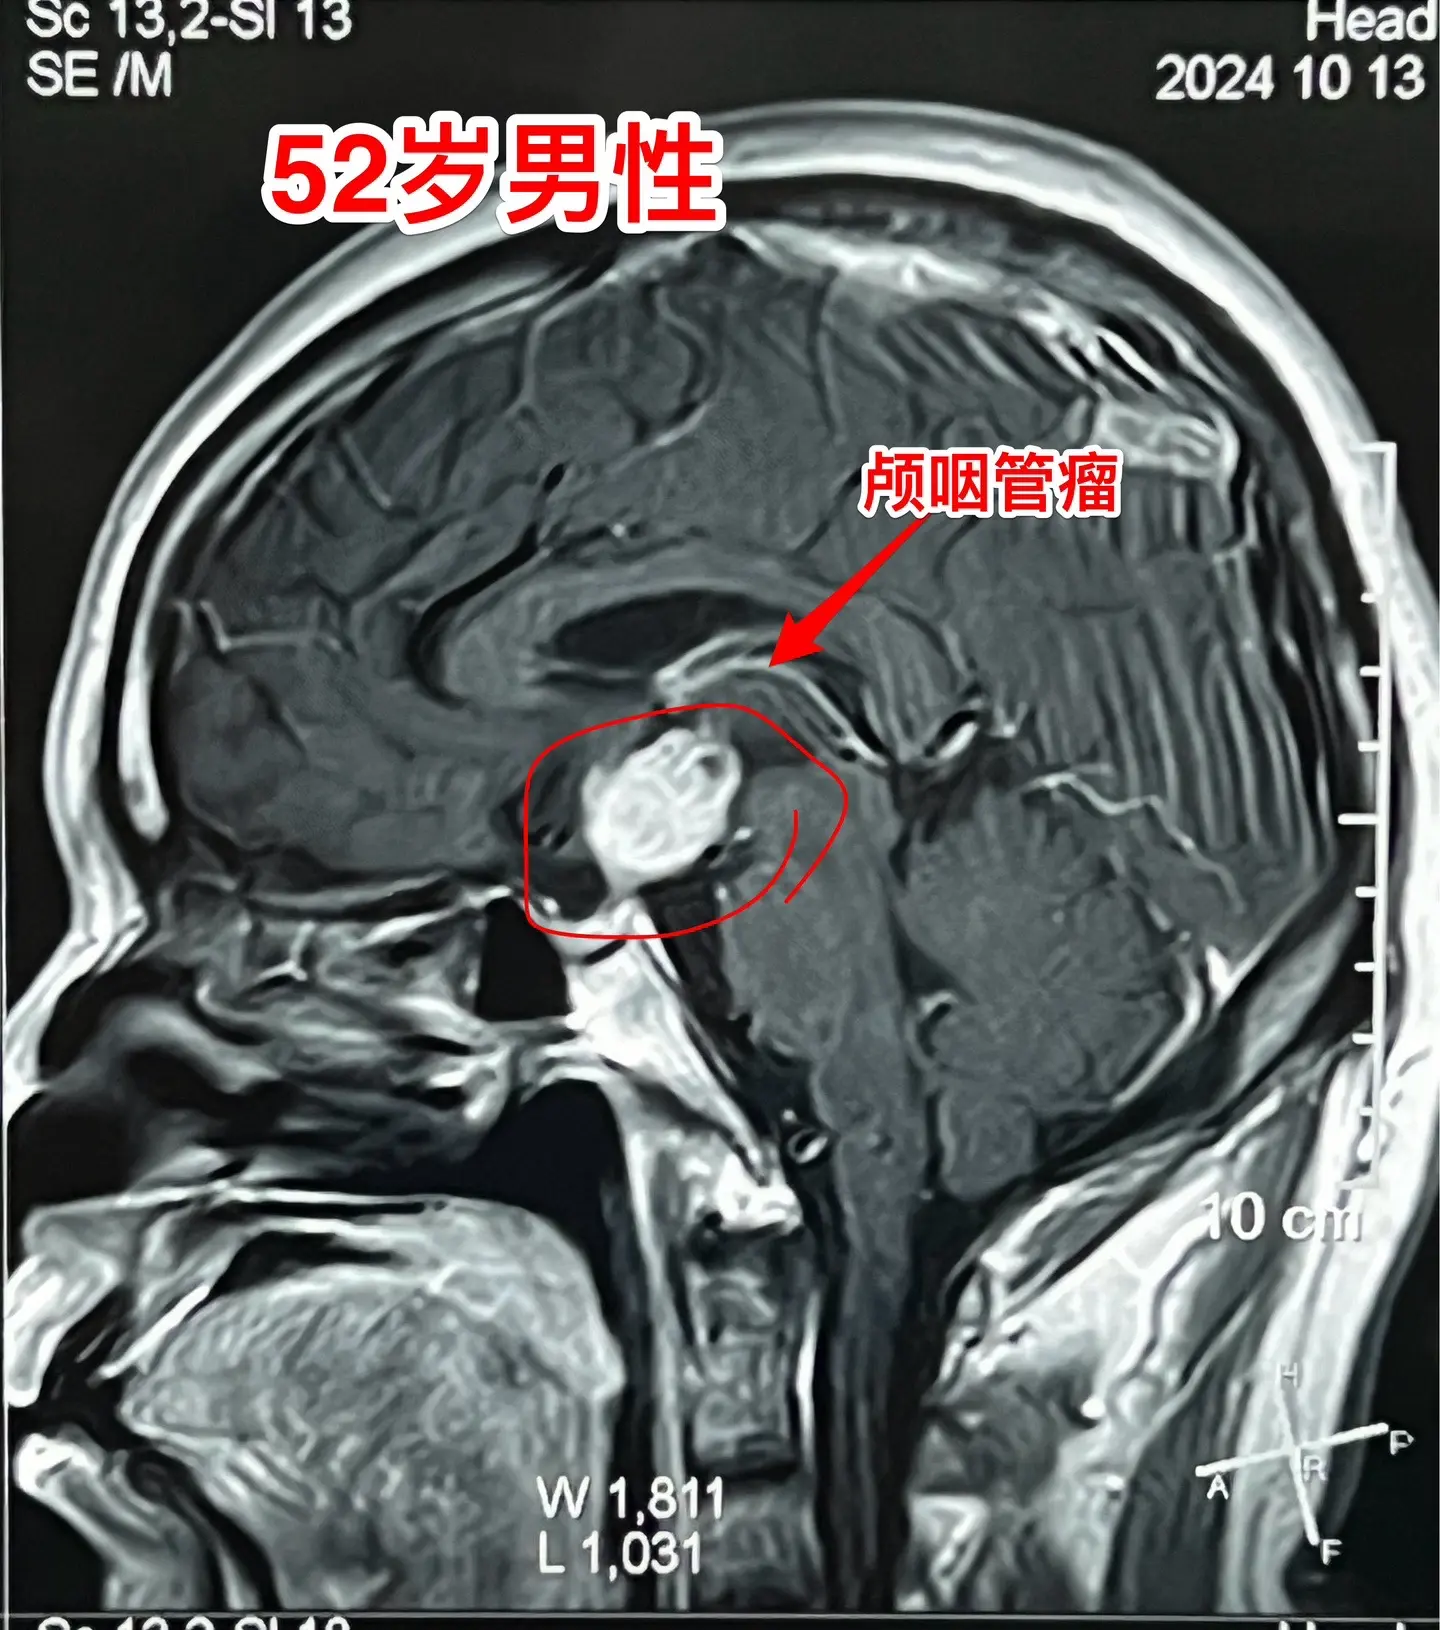

乳头型颅咽管瘤。52岁的重庆市男性,因为头痛到医院检查磁共振,居然发现脑部有个颅咽管瘤,典型的乳头型颅咽管瘤。CT显示肿瘤没有钙化,基本就是一个实性肿瘤。 患者的女儿是重庆市某医院的手术室护士。通过重庆三博脑科医院的医生找到我,来北京三博脑科医院作手术。10月18日顺利切除肿瘤,垂体柄保留约50%。 针对乳头型颅咽管瘤,第一选择还是手术切除,而不是首选靶向药(有的患者对手术感到害怕,希望用药物治疗颅咽管瘤)。